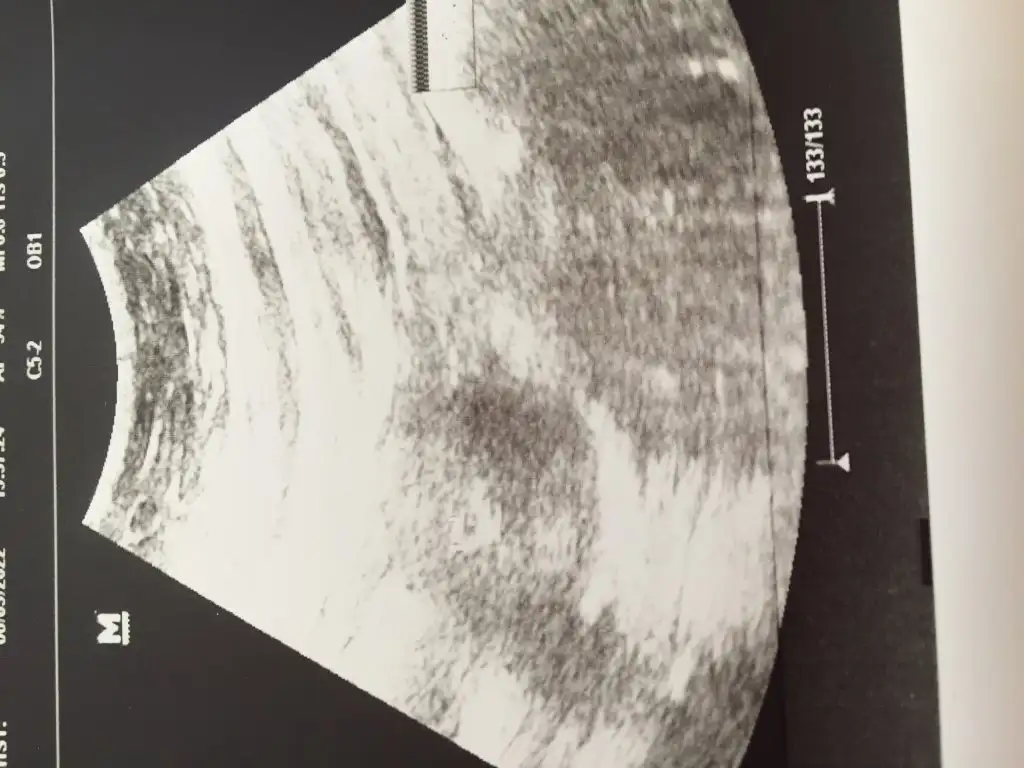

Eklentiler

• 22C9113A-E5D0-4121-8E6B-B630E0E29943.webp

22C9113A-E5D0-4121-8E6B-B630E0E29943.webp

29,3 KB · Görüntüleme: 56